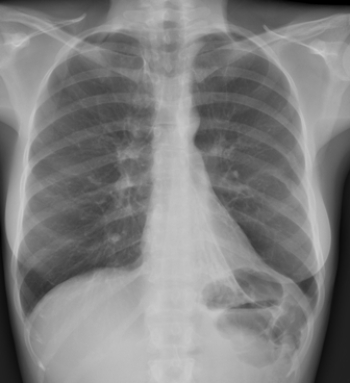

This frontal radiograph suggests an increase in lung density associated with an apparent silhouette sign along the right border of the heart. However, after a lateral view was also examined, the radiologist concluded that the patient's lungs were normal. Why?